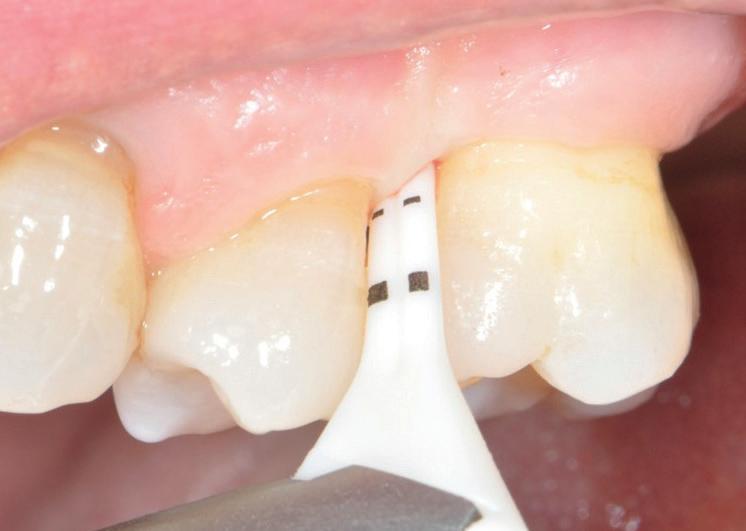

RECONSTITUIREA țesuturilor moi periimplantare. Scopul acestui raport de caz este de a demonstra procedurile chirurgicale utilizate pentru corectarea unui defect al țesuturilor moi periimplantare folosind țesutul moale interdentar în combinație cu tuberozitatea ca locație donatoare de țesut conjunctiv, utilizând o abordare prin tunelizare într-o zonă estetică.

REABILITAREA implanturilor în zona estetică. Acest articol detaliază două cazuri rezolvate prin tehnica extracției parțiale, finalizate fără grefarea compartimentului dintre implant și scut, și monitorizate cinci ani, dovedind stabilitatea volumetrică a țesuturilor moi și dure în timp.